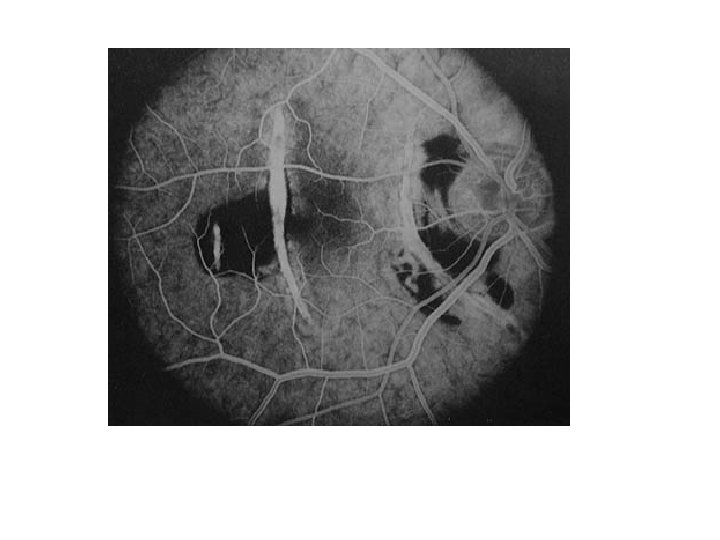

THE PICTURE AND FLUORESCEIN ANGIOGRAPHY ARE TAKEN FROM A PATIENT COMPLAINING OF DISTORTED RIGHT

THE PICTURE AND FLUORESCEIN ANGIOGRAPHY ARE TAKEN FROM A PATIENT COMPLAINING OF DISTORTED RIGHT VISION. A. WHAT PHASE IS THE FLUORESCEIN ANGIOGRAPHY? B. WHAT IS THE DIAGNOSIS? C. WHAT UNDERLYING MEDICAL CONDITION

• Venous phase • Macroaneurysm • Hypertention

Choroidal rupture